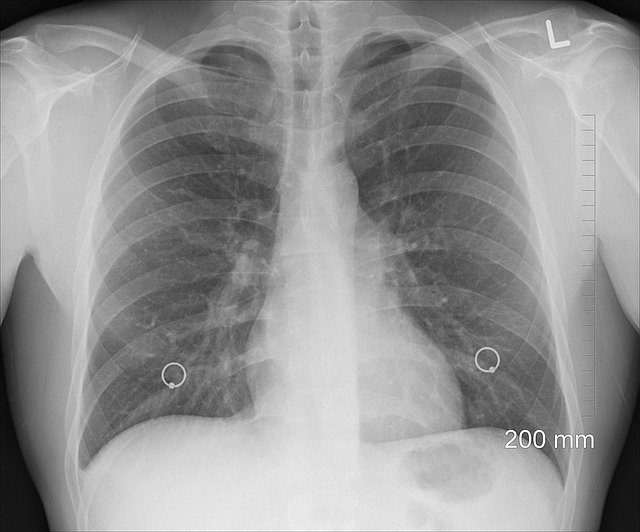

폐섬유증이란

폐조직이 굳어서 호흡장애를 일으키는 호흡기 질환 입니다.

폐의 섬유질 조직이 쌓여 폐가 굳어가는걸 폐섬유화라고 하는데 폐섬유화로 인해 폐벽이 두꺼워지면서 산소량이 줄어 들게 됩니다.

폐섬유증 증상으로는 폐에 들어가는 산소량이 줄어들기 때문에 계속 숨이 차오르게 되는 증상이 나타납니다.

폐섬유증 원인으로는 아직 밝혀진것이 없고 흡연, 바이러스, 유전 등이 영향을 끼칠 수 있다고 하나 정확하게 밝혀지지 않았습니다.

폐섬유증 치료법이 없으며 대부분 5~7년을 넘기기 힘들다고 합니다.

폐 이식을 시도하기도 한다고 합니다.

코로나 후유증으로 폐섬유증을 유발한다는 연구 결과도 나오고 있습니다.

폐암 만큼이나 난치성 희귀 질환으로 치료 방법이 없고 폐섬유화 증상을 완화 시키는게 전부지만 생존 기간이 점점 늘어나는걸 보면 미래에는 희망이 보일것이라고 생각 됩니다.